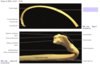

Atlas (C1)

Anterior Arch

Atlas (C1)

Posterior Arch

Atlas (C1)

Lateral Mass

Atlas (C1)

Groove for the Verterbral artery

Atlas (C1)

Superior Articulating Process (articulates with Occipital Condyles)

Atlas (C1)

Transverse Foramen (transmits Vertebral artery)